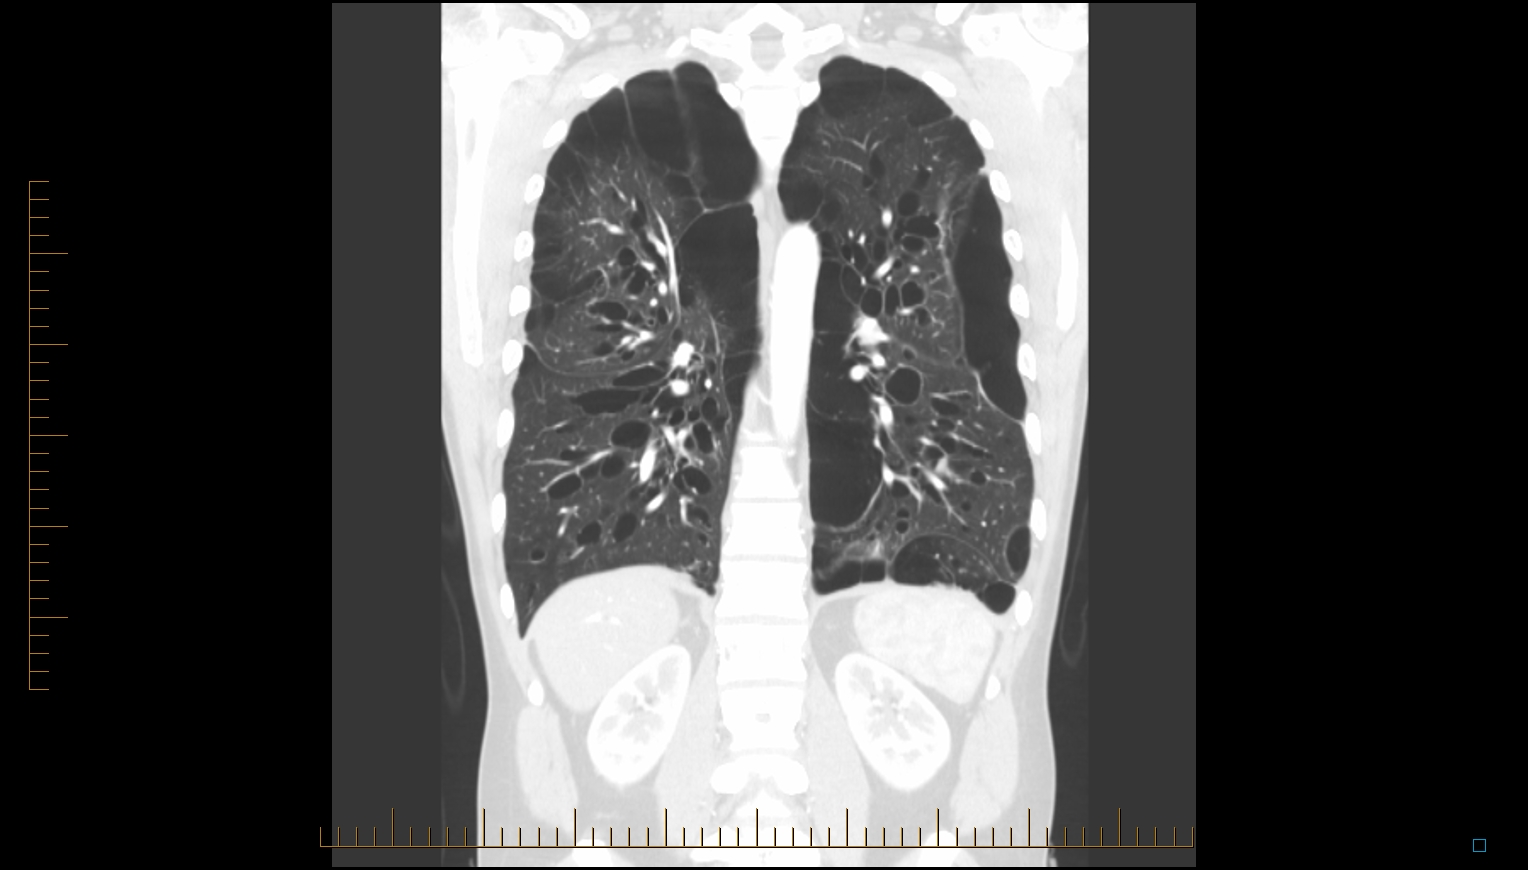

Idiopathic Bullous Emphysema (Vanishing Lung Syndrome)